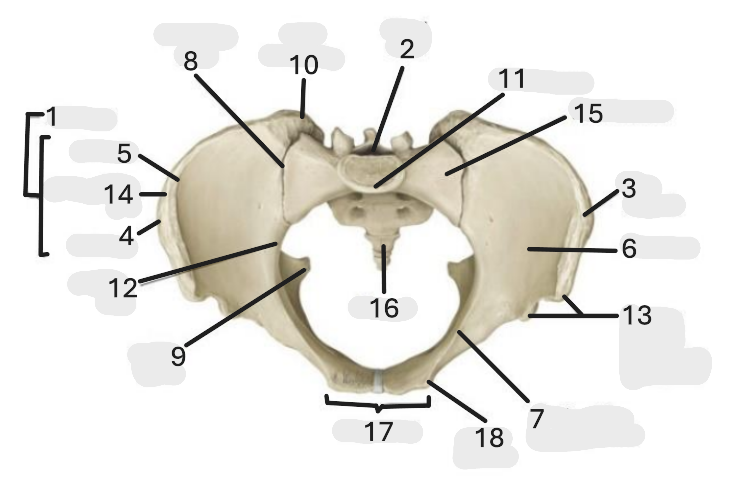

Where is the pelvic inlet

1

Where is the sacro-iliac joint

2

Where is the pubic tubercle

3

Where are the S1 body

4

Where is the ischial spine

5

Where is the ala of sacrum

6

Where is the anterior superior iliac spine

7

Where is the ischiopubic ramus

8

Where is the coccyx

9

Where is the obturator foramen

10

Where is the pubic symphysis

11

Where is the ischial tuberosity

12